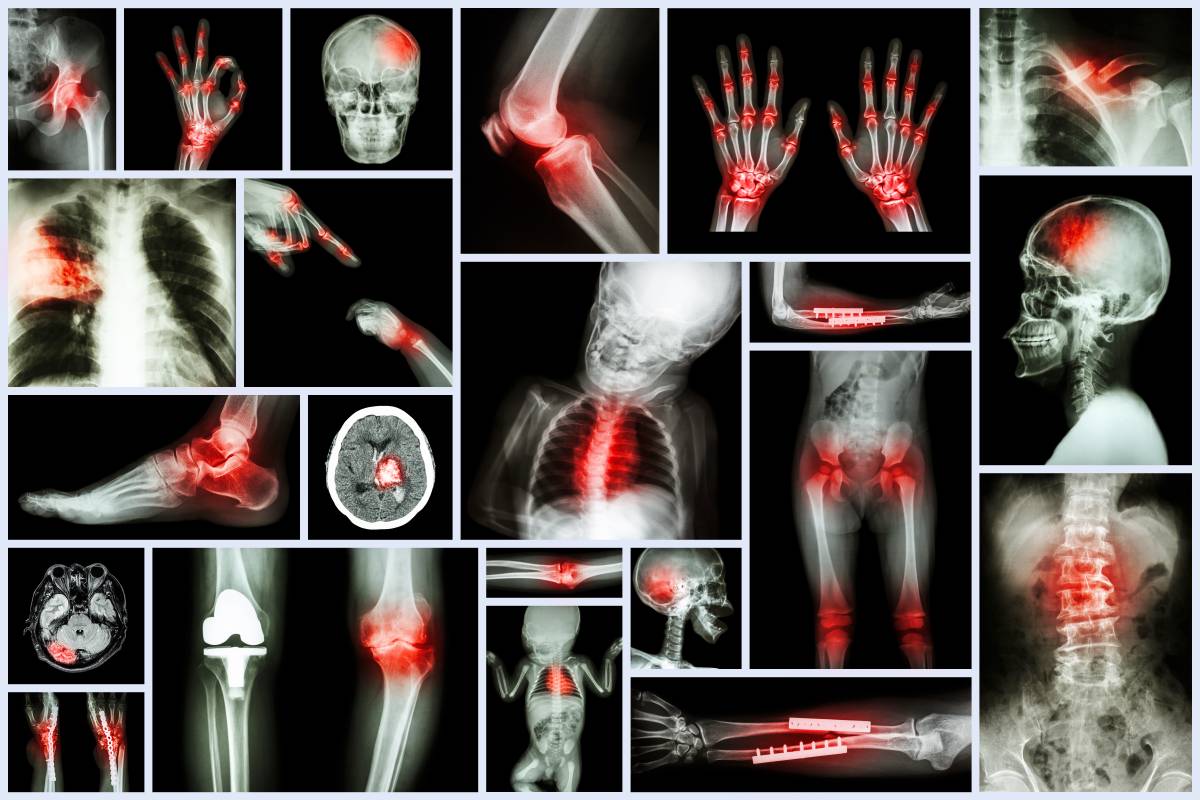

2021-10-11 15:53:00入冬以来,厚重的衣服让人们的行动变得相对笨拙,加之一些路面可能会有冰雪覆盖,相对较滑,因此而发生摔倒引发骨折的病例也增多了起来。

骨折以后及时进行治疗,大多数患者可以恢复原来的肢体功能。但“伤筋动骨一百天”,骨折的愈合需要一个过程,一般经过治疗后,需要长时间卧床,这就增加了膝关节粘连、僵硬及关节周围肌肉萎缩等并发症的发生几率,给膝关节功能恢复增加了一定的难度。那么,骨折大约需要多久可以康复?进行哪些训练可以加速康复进程呢?一起来了解一下吧。